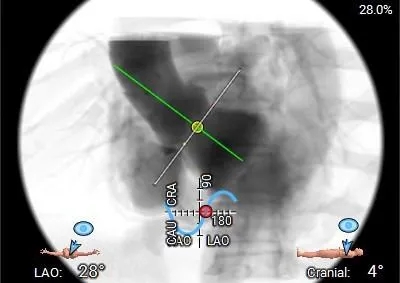

工作体位

右窦居中

左冠切线

左右重叠